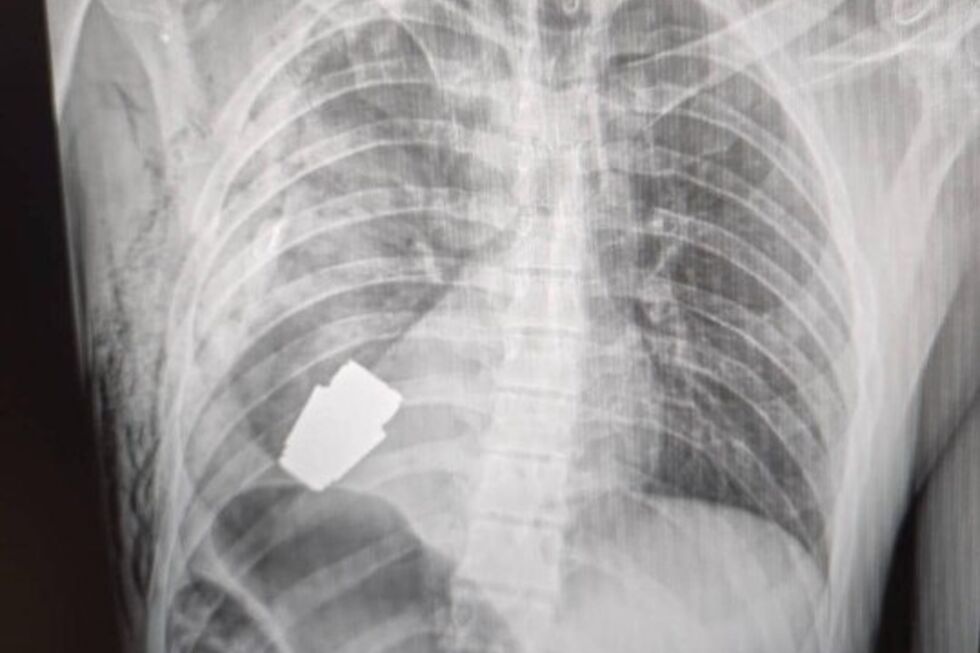

A vice-ministra da Defesa ucraniana, Hanna Maliar, partilhou na sua página de Facebook um imagens de um raio-x onde é possível ver a munição alocada no peito do soldado: "Médicos militares realizaram uma operação para retirar uma granada VOG, que não deflagrou, do corpo do soldado", descreveu.

Este tipo de granada tem um calibre de 40 mm e é disparada a partir de lança-granadas colocados em armas de assalto.